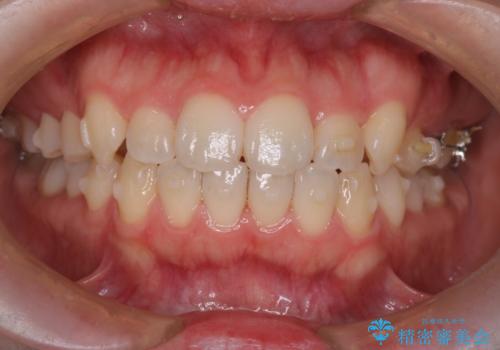

- 患者様は歯並びの乱れを気にされて来院されました。特に小臼歯の捻転(ねじれ)が強く、見た目だけでなく噛み合わせにも影響がありました。できるだけ目立たない方法を希望されていたため、インビザライン(マウスピース矯正)を基本としつつ、より精密な動きが必要な部分にはワイヤー矯正を併用する計画を立てました。また、小臼歯の捻転については**部分矯正(MTM:Minor Tooth Movement)**を取り入れ、効率的に改善を目指しました。

まず、全体の歯並びを整えるためにインビザラインを使用し、徐々に理想的な位置へと歯を移動させました。一方で、ねじれの強い小臼歯に対しては、**部分的なワイヤー矯正(MTM)**を行い、より精密なコントロールを実施。約2年の治療期間を経て、歯並びと噛み合わせが整い、見た目の美しさだけでなく、機能的な改善も達成しました。患者様からは「自然な仕上がりで、自信を持って笑えるようになった」と喜びの声をいただきました。